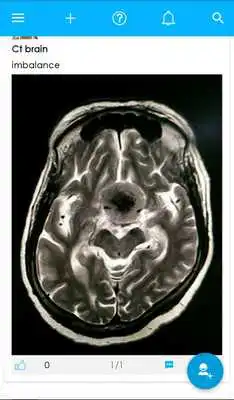

You can share radiographs, CT scan , MRI , Mammography, ultrasound, nuclear imaging and PET scan etc images.